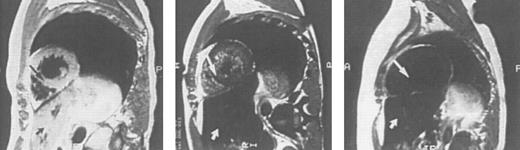

Imaging of tissue iron.Computed tomography,170-174 nuclear resonance scattering (NRS) from manganese-56,175 and the most widely used modality, magnetic resonance imaging,176-193 have all been used to evaluate tissue iron stores in vitro and in vivo, but none is clinically available for the measurement of hepatic iron concentrations. Biopsy-demonstrated reductions in hepatic iron have been reflected by magnetic resonance imaging (MRI) in individual patients192 (Fig 3), but correlations between hepatic iron concentrations determined by biopsy and those estimated by magnetic resonance have varied with differences in both equipment and method. Magnetic resonance represents the only imaging method in clinical use with the potential to detect iron within the heart189,192,193 (Fig 4). Although imprecision in the quantitation of cardiac iron obtained at biopsy194,195 prevents direct correlation with values of cardiac iron estimated by MRI in humans, good correlation between MRI-derived, and biopsy-determined, cardiac iron has been observed in a thalassemic mouse model.193 Furthermore, MRI changes consistent with the reduction of cardiac iron (Fig 5) that are paralleled by improvement in cardiac function have been reported in individual patients.192 Similarly, MRI studies of the iron-loaded anterior pituitary gland196,197 have reported variations in pituitary iron that are correlated with pituitary reserve in individual patients with thalassemia.198 In summary, although many studies show that MRI can reflect the presence of, and changes in, tissue iron in vivo, this method has not been validated as one that provides measurements of tissue iron that are quantitatively equivalent to those determined at tissue biopsy.

Sagittal MRI of the heart in three patients with homozygous β thalassemia and transfusional iron overload. (A, left) Normal signal from the septum (long arrow) and posterior wall of the heart, consistent with the presence of very mild cardiac iron loading, in a transfused patient regularly complianct with iron chelating therapy. The homogenous signal of the liver, consistent with very mild iron loading in this organ (short arrow), is also seen below the image of the heart. (B, middle): Imhomogenity of signal from the septum (long arrow) and posterior wall, consistent with moderate iron deposition in a transfused patient erratically compliant with iron chelating therapy. Loss of liver signal (short arrow) is consistent with heavier iron loading in this organ. (C, right): Absence of signal from the septum (arrow), posterior wall and liver (short arrow), compatible with heavy iron deposition in a transfused patient who has been noncompliant with iron chelating therapy over several years.

Sagittal MRI of cardiac iron before (left) and after (right) therapy with the orally active iron chelating agent deferiprone in the same patient with homozygous β thalassemia whose liver histology and hepatic MRI are shown in Fig 3. Imhomogenity of cardiac signal in the MRI on the left is compatible with significant iron deposition, while improvement in signal intensity after nine months of chelating therapy indicates that the cardiac iron content is reduced compared with that of the previous study. (Reprinted with permission.192 )